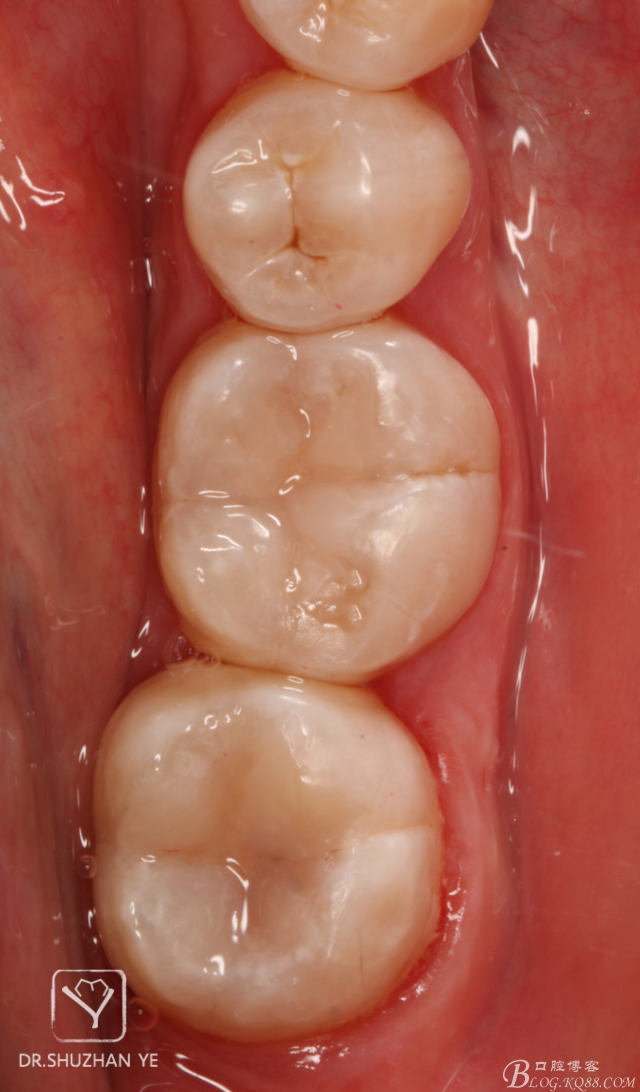

10、拆除橡皮障,初步調(diào)合,修整,拋光

11、復(fù)診拋光完成

總結(jié)體會(huì):印章法對(duì)于頜面窩溝點(diǎn)隙的齲壞,且頜面完整的病例比較適用,提高了窩溝塑性的效率和準(zhǔn)確性,能大大節(jié)約臨床操作時(shí)間,而并且因?yàn)槭侵苯釉螒B(tài)復(fù)制,所以完成后基本不需要調(diào)合,能節(jié)約不少時(shí)間,也在最大程度上保護(hù)了原有的咬合關(guān)系,同時(shí),在美觀上也能符合患者及醫(yī)生自己的要求。